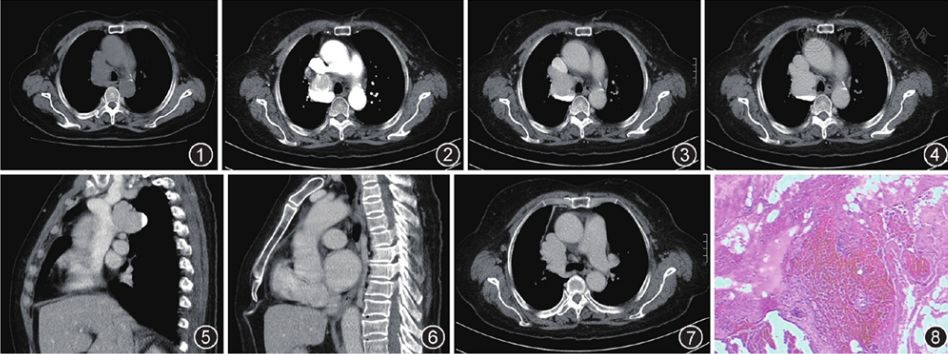

病例报告奇静脉海绵状血管瘤一例

罕见后纵隔特发性奇静脉瘤一例